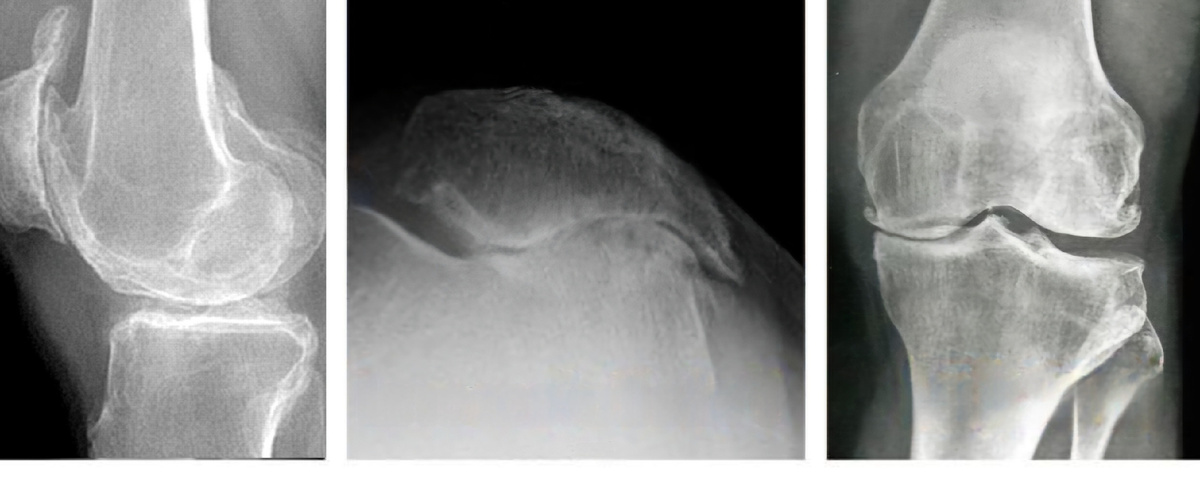

Рентгенография коленного сустава в 3х проекциях. Показаны деформирующие изменения в суставе.